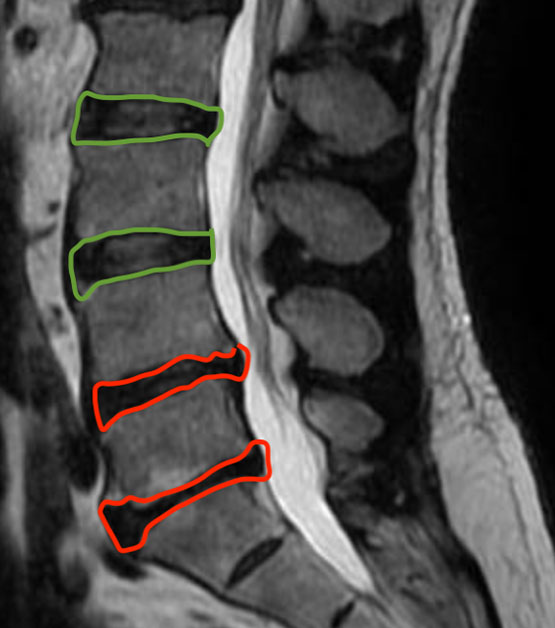

Decidido a encontrar uma solução duradoura, realizou uma ressonância magnética da coluna lombar. O diagnóstico revelou uma discopatia degenerativa avançada nas regiões L4-L5 e L5-S1, indicando a necessidade de uma abordagem mais assertiva.

Ressonância da coluna lombar evidenciando o desgaste avançado nos discos (vermelho) em comparação aos discos sadios (verde).